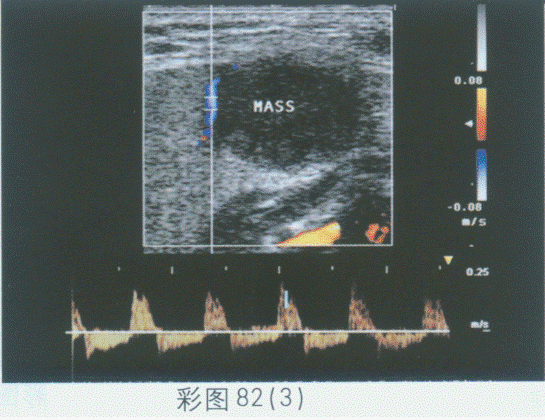

临床资料:女,28岁,右颌下肿、不适两月余。超声综合描述:右侧颌下腺可见1.5cm×1.1cm长圆形低回声,边界清晰,形态规则,内回声不均,后方声加强,CDFI:其内及周边可见血流信号。见下图及彩图82。

超声提示()。